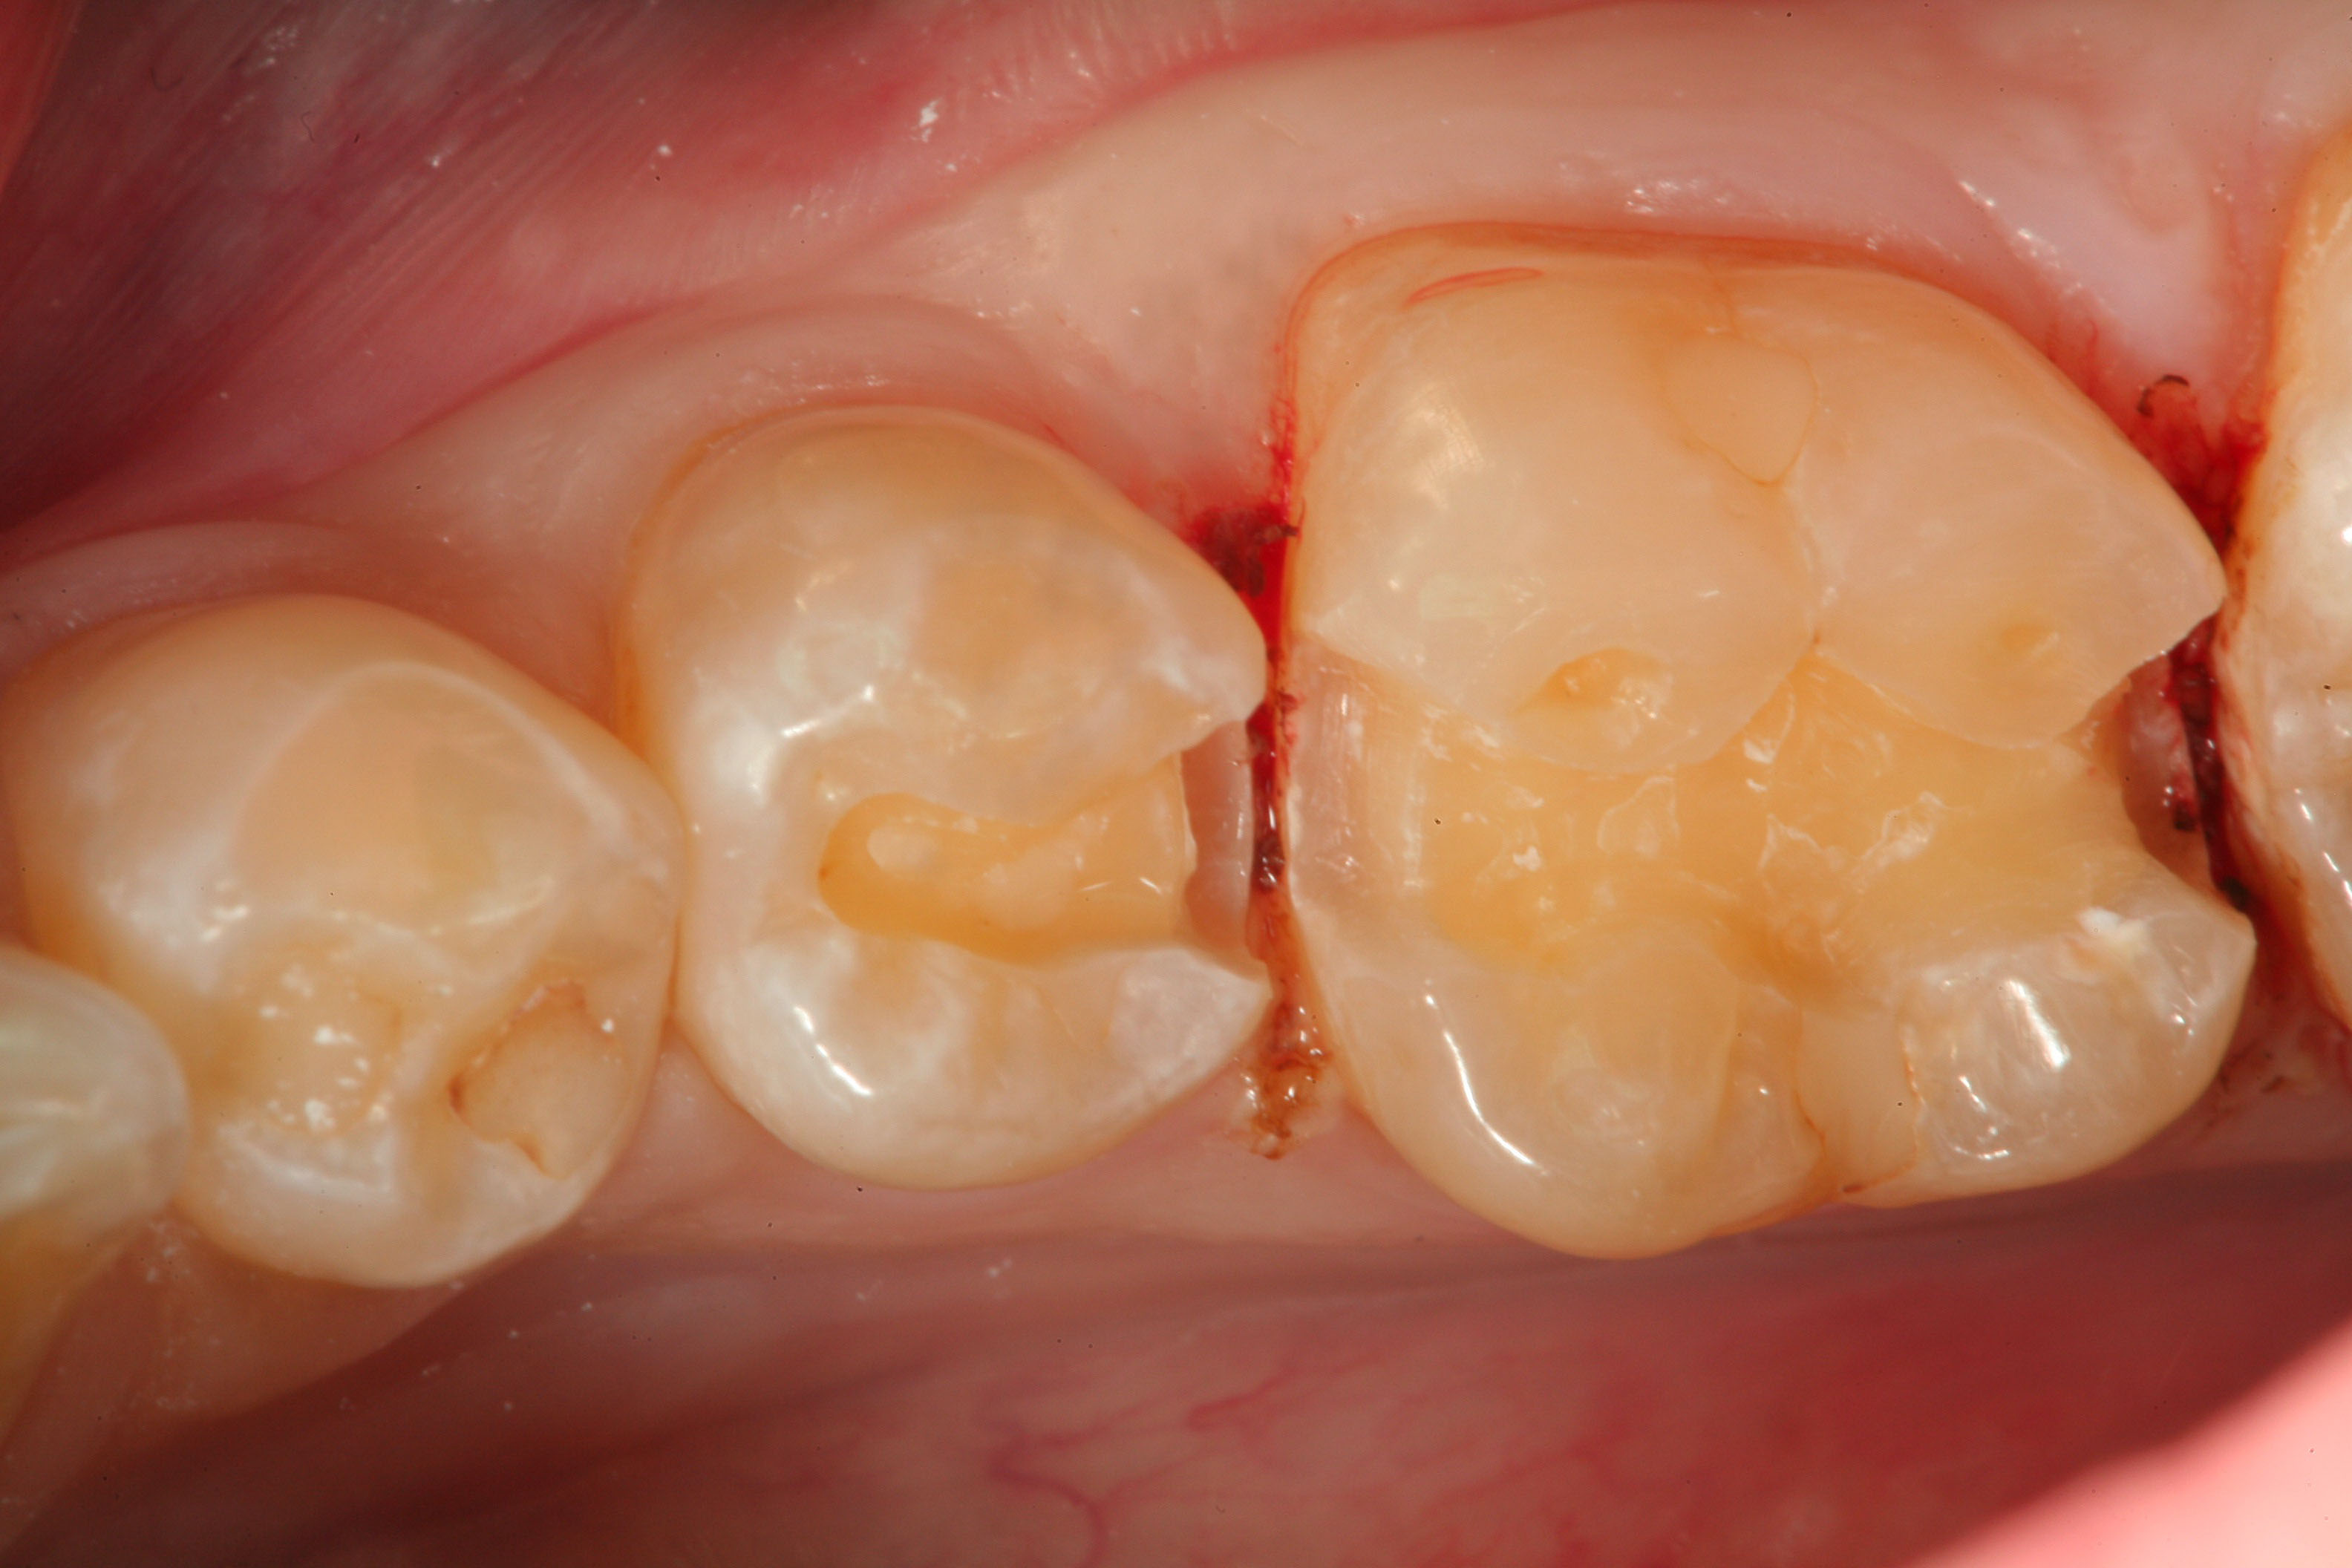

Fig 20. A distal-occlusal cavity preparation in tooth No. 29 and a mesial-occlusal-distal cavity preparation in tooth No. 30 are both shown from the occlusal aspect. A diode laser has been used interproximally to create supragingival margins to aid in precise gingival placement of the restorative material.

Figure 20